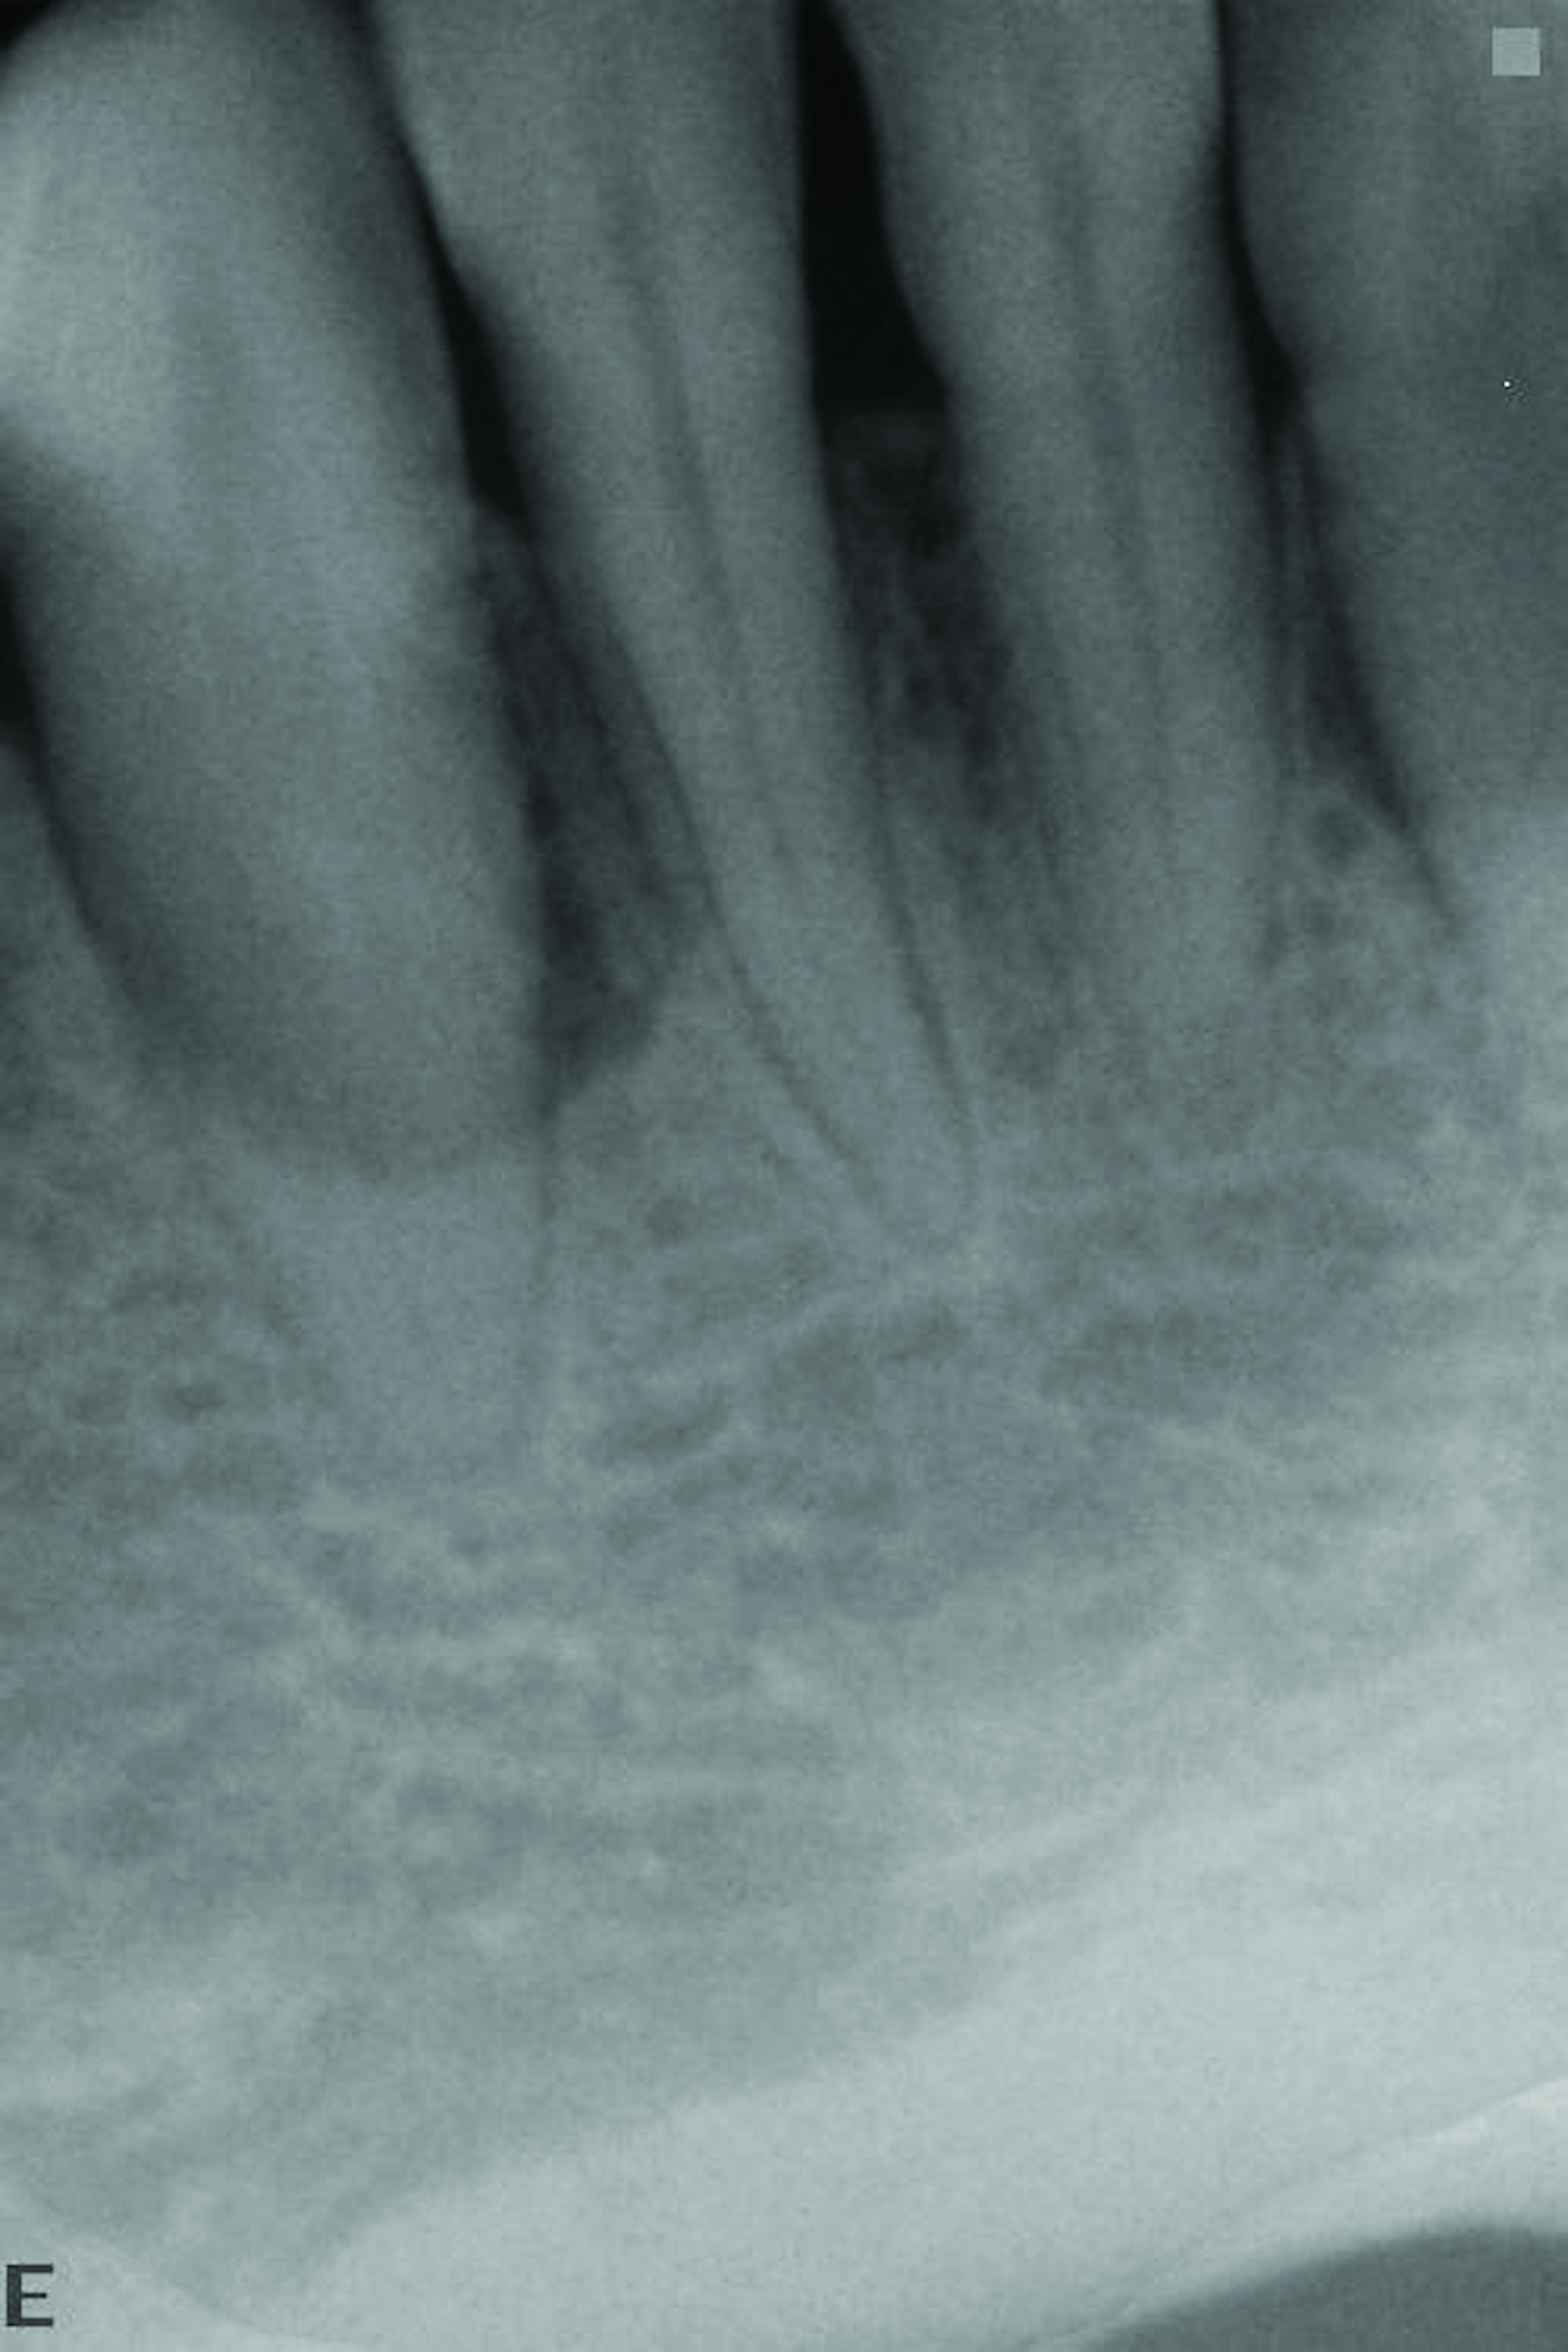

The 13-month postoperative radiograph. Significant regeneration is suggested.

Figure 20

The pretreatment radiograph suggesting more than 2 mm of subantral alveolar bone.

Figure 21